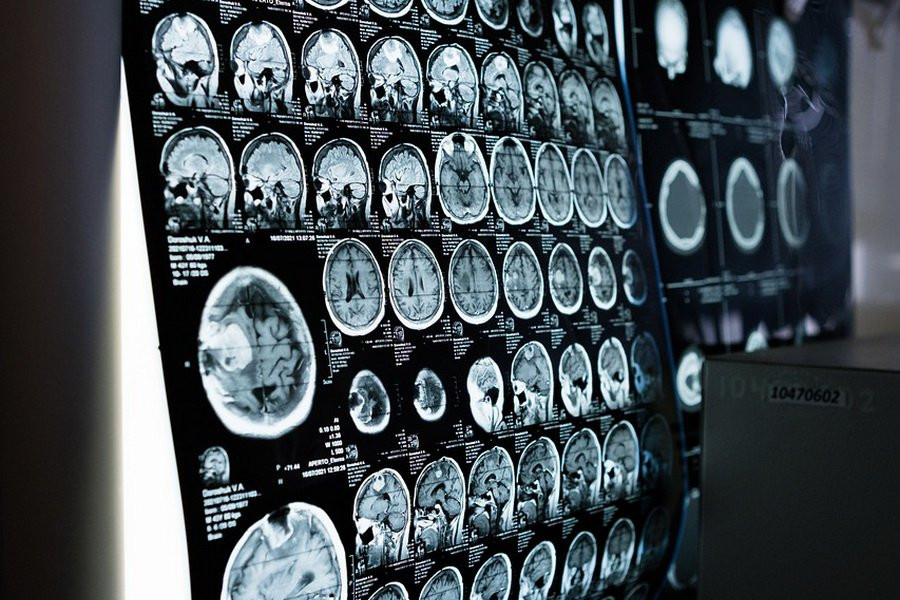

В статье, опубликованной в журнале HealthDay, раскрывается интересная взаимосвязь между уровнем сахара в крови и темпами старения мозга. Согласно проведенному анализу МРТ-снимков более 31 тысячи британцев в возрасте от 40 до 70 лет, была выявлена четкая закономерность: у людей с диабетом 2-го типа мозг в среднем был на 4 года старше, чем у их здоровых сверстников.

Более того, даже у тех, кто находится в предиабетном состоянии, биологический возраст мозга был на полгода больше, чем у здоровых людей. Это наглядно демонстрирует, что высокий уровень сахара в крови оказывает негативное влияние на процессы, происходящие в головном мозге.

Вместе с тем, исследование показало, что здоровый образ жизни может защитить от ускоренного старения мозга. Диабетики, которые вели физически активный образ жизни, не курили и не употребляли алкоголь, демонстрировали нормальное состояние мозга. Это указывает на важность профилактики и контроля уровня сахара для сохранения когнитивных способностей.

Учитывая, что диабет значительно повышает риск развития деменции, данные результаты могут помочь в разработке эффективных стратегий по предотвращению этого серьезного неврологического заболевания. Понимание механизмов, связывающих диабет и старение мозга, позволит разработать более действенные методы профилактики и лечения.